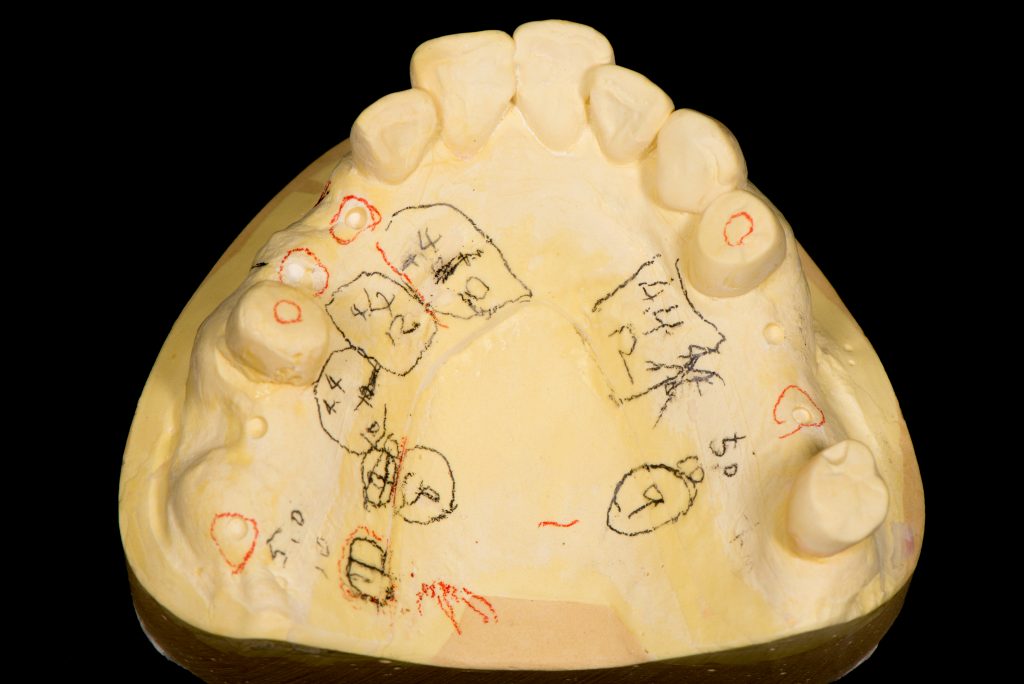

本数が多い為、最終的な歯の位置を考えてインプラントをする必要があります。その為、サージカルガイドと呼ばれる物を作製し、インプラントの位置を決めCT撮影を行いオペを行いました。

処置前の歯型(治療方針が書かれています)